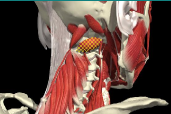

ACCURACY OF LOCALIZATION - SCALENES

ACCURACY OF LOCALIZATION LEVATOR SCAPULAE

LOCALIZATION OF MUSCLES IN DEEPER LAYERS

Layer 1

Layer 2

Layer 3

Splenius Capitis

Semispinalis Capitis

Longissimus Capitus

Semispinalis Cervicis

ACCURACY OF LOCALIZATION – DEEPER LAYERS